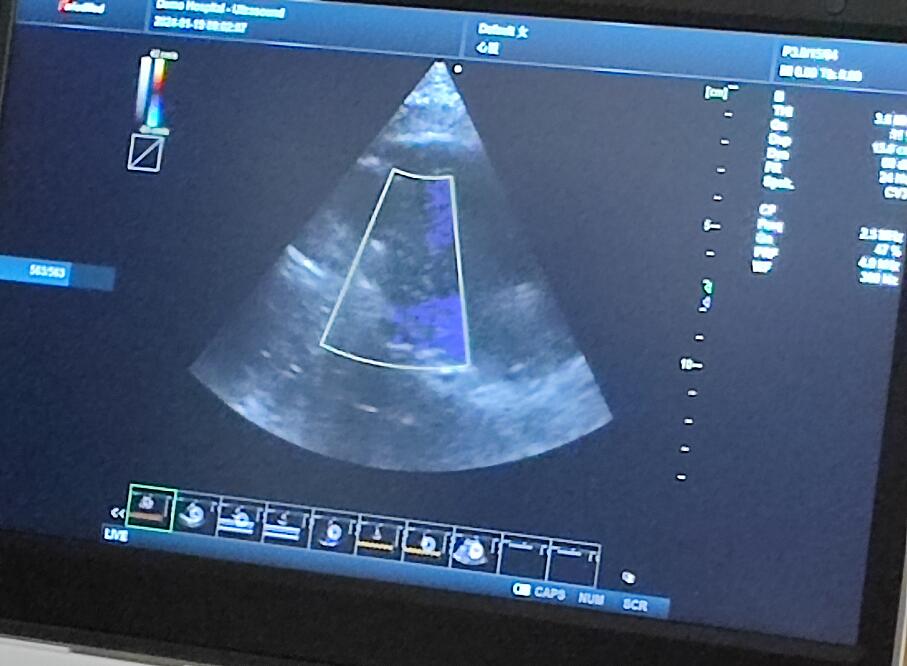

當(dāng)天的超聲培訓(xùn)現(xiàn)場氣氛熱烈非凡,來自普邁思醫(yī)療事業(yè)部的同仁們紛紛積極參與,滿懷期待地聚集在講臺周圍,他們的眼神充滿了對新知識的渴望和對技術(shù)提升的執(zhí)著追求。老師身邊里三層外三層圍滿了學(xué)員,大家或是聚精會神聆聽講解,或是踴躍提問,交流互動,濃厚的學(xué)習(xí)氛圍讓整個場地顯得熱鬧非凡,盡管空間狹小,但阻擋不住的是每一位參與者內(nèi)心深處對于專業(yè)技能提升的決心與毅力。

授課的專家老師被這股澎湃的學(xué)習(xí)熱情深深打動,她的臉上洋溢著欣慰和鼓舞的笑容。面對這樣一群如饑似渴的學(xué)子,老師更是傾盡全力,毫無保留地將自己豐富的臨床經(jīng)驗和深厚的專業(yè)理論知識悉數(shù)傳授,詳細解答每一個問題,用心指導(dǎo)每一次操作演練。她表示,普邁思醫(yī)療事業(yè)部團隊展現(xiàn)出的這種敬業(yè)精神和積極向上的風(fēng)貌讓她深受感染,還給予了他們高度評價和嘉許。